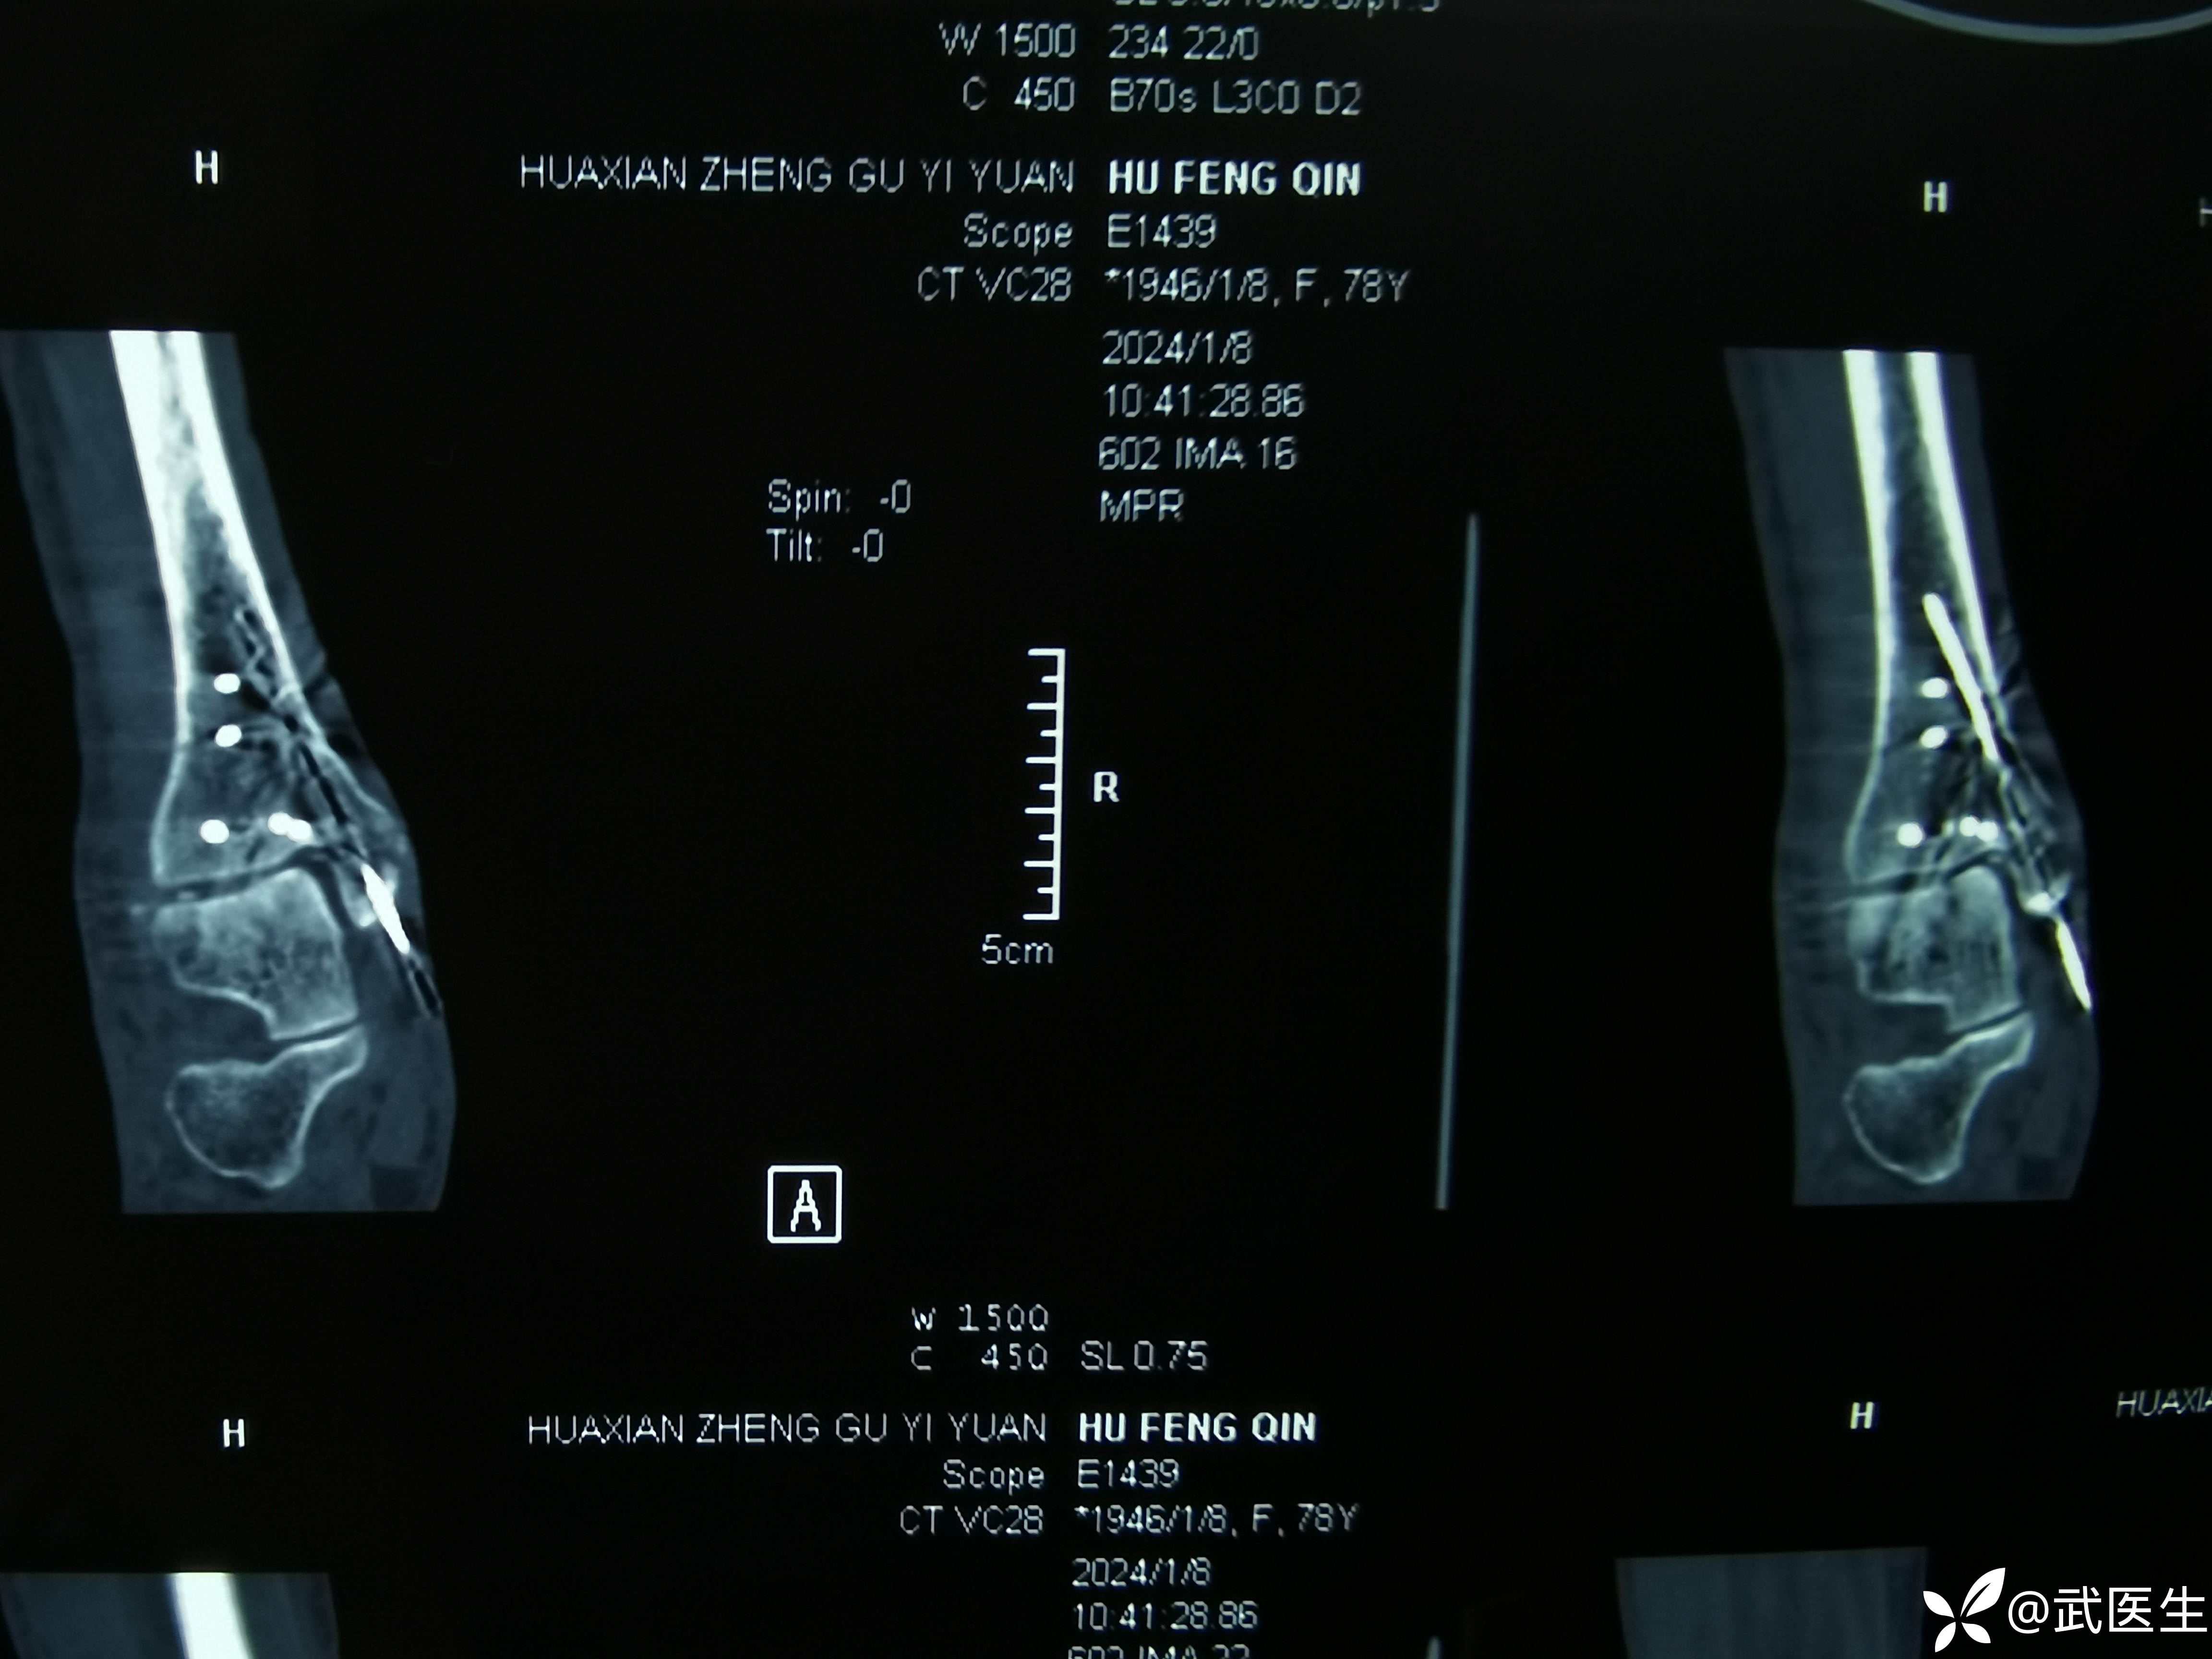

术后ct,复位还行